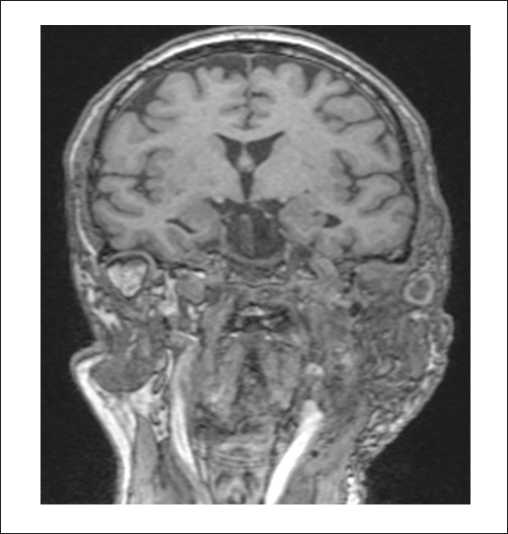

На МРТ головного мозга и мягких тканей шеи определялось распространение образования на капсулу улитки и на область правой мостомозжечковой цистерны (рисунки 6, 8, 9). Соответствующие отделы головного мозга не изменены. Определялись признаки распространения процесса по ходу внутренней яремной вены (1). Просвет внутренней яремной вены в этой области не прослеживался (2) (рисунок 7).

Рисунок 6. МРТ головного мозга и мягких тканей шеи, Т2-ВИ с подавлением сигнала от жировой ткани, в корональной плоскости. Параганглиома, тип С: определяется распространение образования на капсулу улитки.

Рисунок 7. МРТ головного мозга и мягких тканей шеи, Т2-ВИс подавлением сигнала от жировой ткани, в корональной плоскости. Параганглиома, тип С: определяются признаки распространения процесса по ходу внутренней яремной вены каудально до уровня С2, с размером экстракраниального компонента 50х18 мм (1). Просвет внутренней яремной веныв этой области не прослеживается (2), субстенотические отделы существенно не расширены.

Рисунок 8. МРТ головного мозга и мягких тканей шеи, Т2-ВИс подавлением сигнала от жировой ткани, в корональной плоскости. Параганглиома, тип С. Послеоперационный контроль спустя 6 месяцев после хирургического лечения: данныхза рецидив новообразования не выявлено.

Рисунок 9. МРТ головного мозга и мягких тканей шеив аксиальной проекции, Т2-ВИ с подавлением сигналаот жировой ткани, в аксиальной плоскости. Параганглиома, тип С. Послеоперационный контроль спустя 6 месяцев после хирургического лечения: данных за рецидив новообразованияне выявлено.